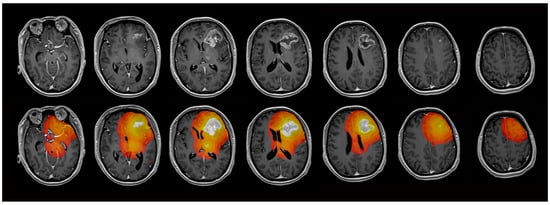

2.4. Image Analysis